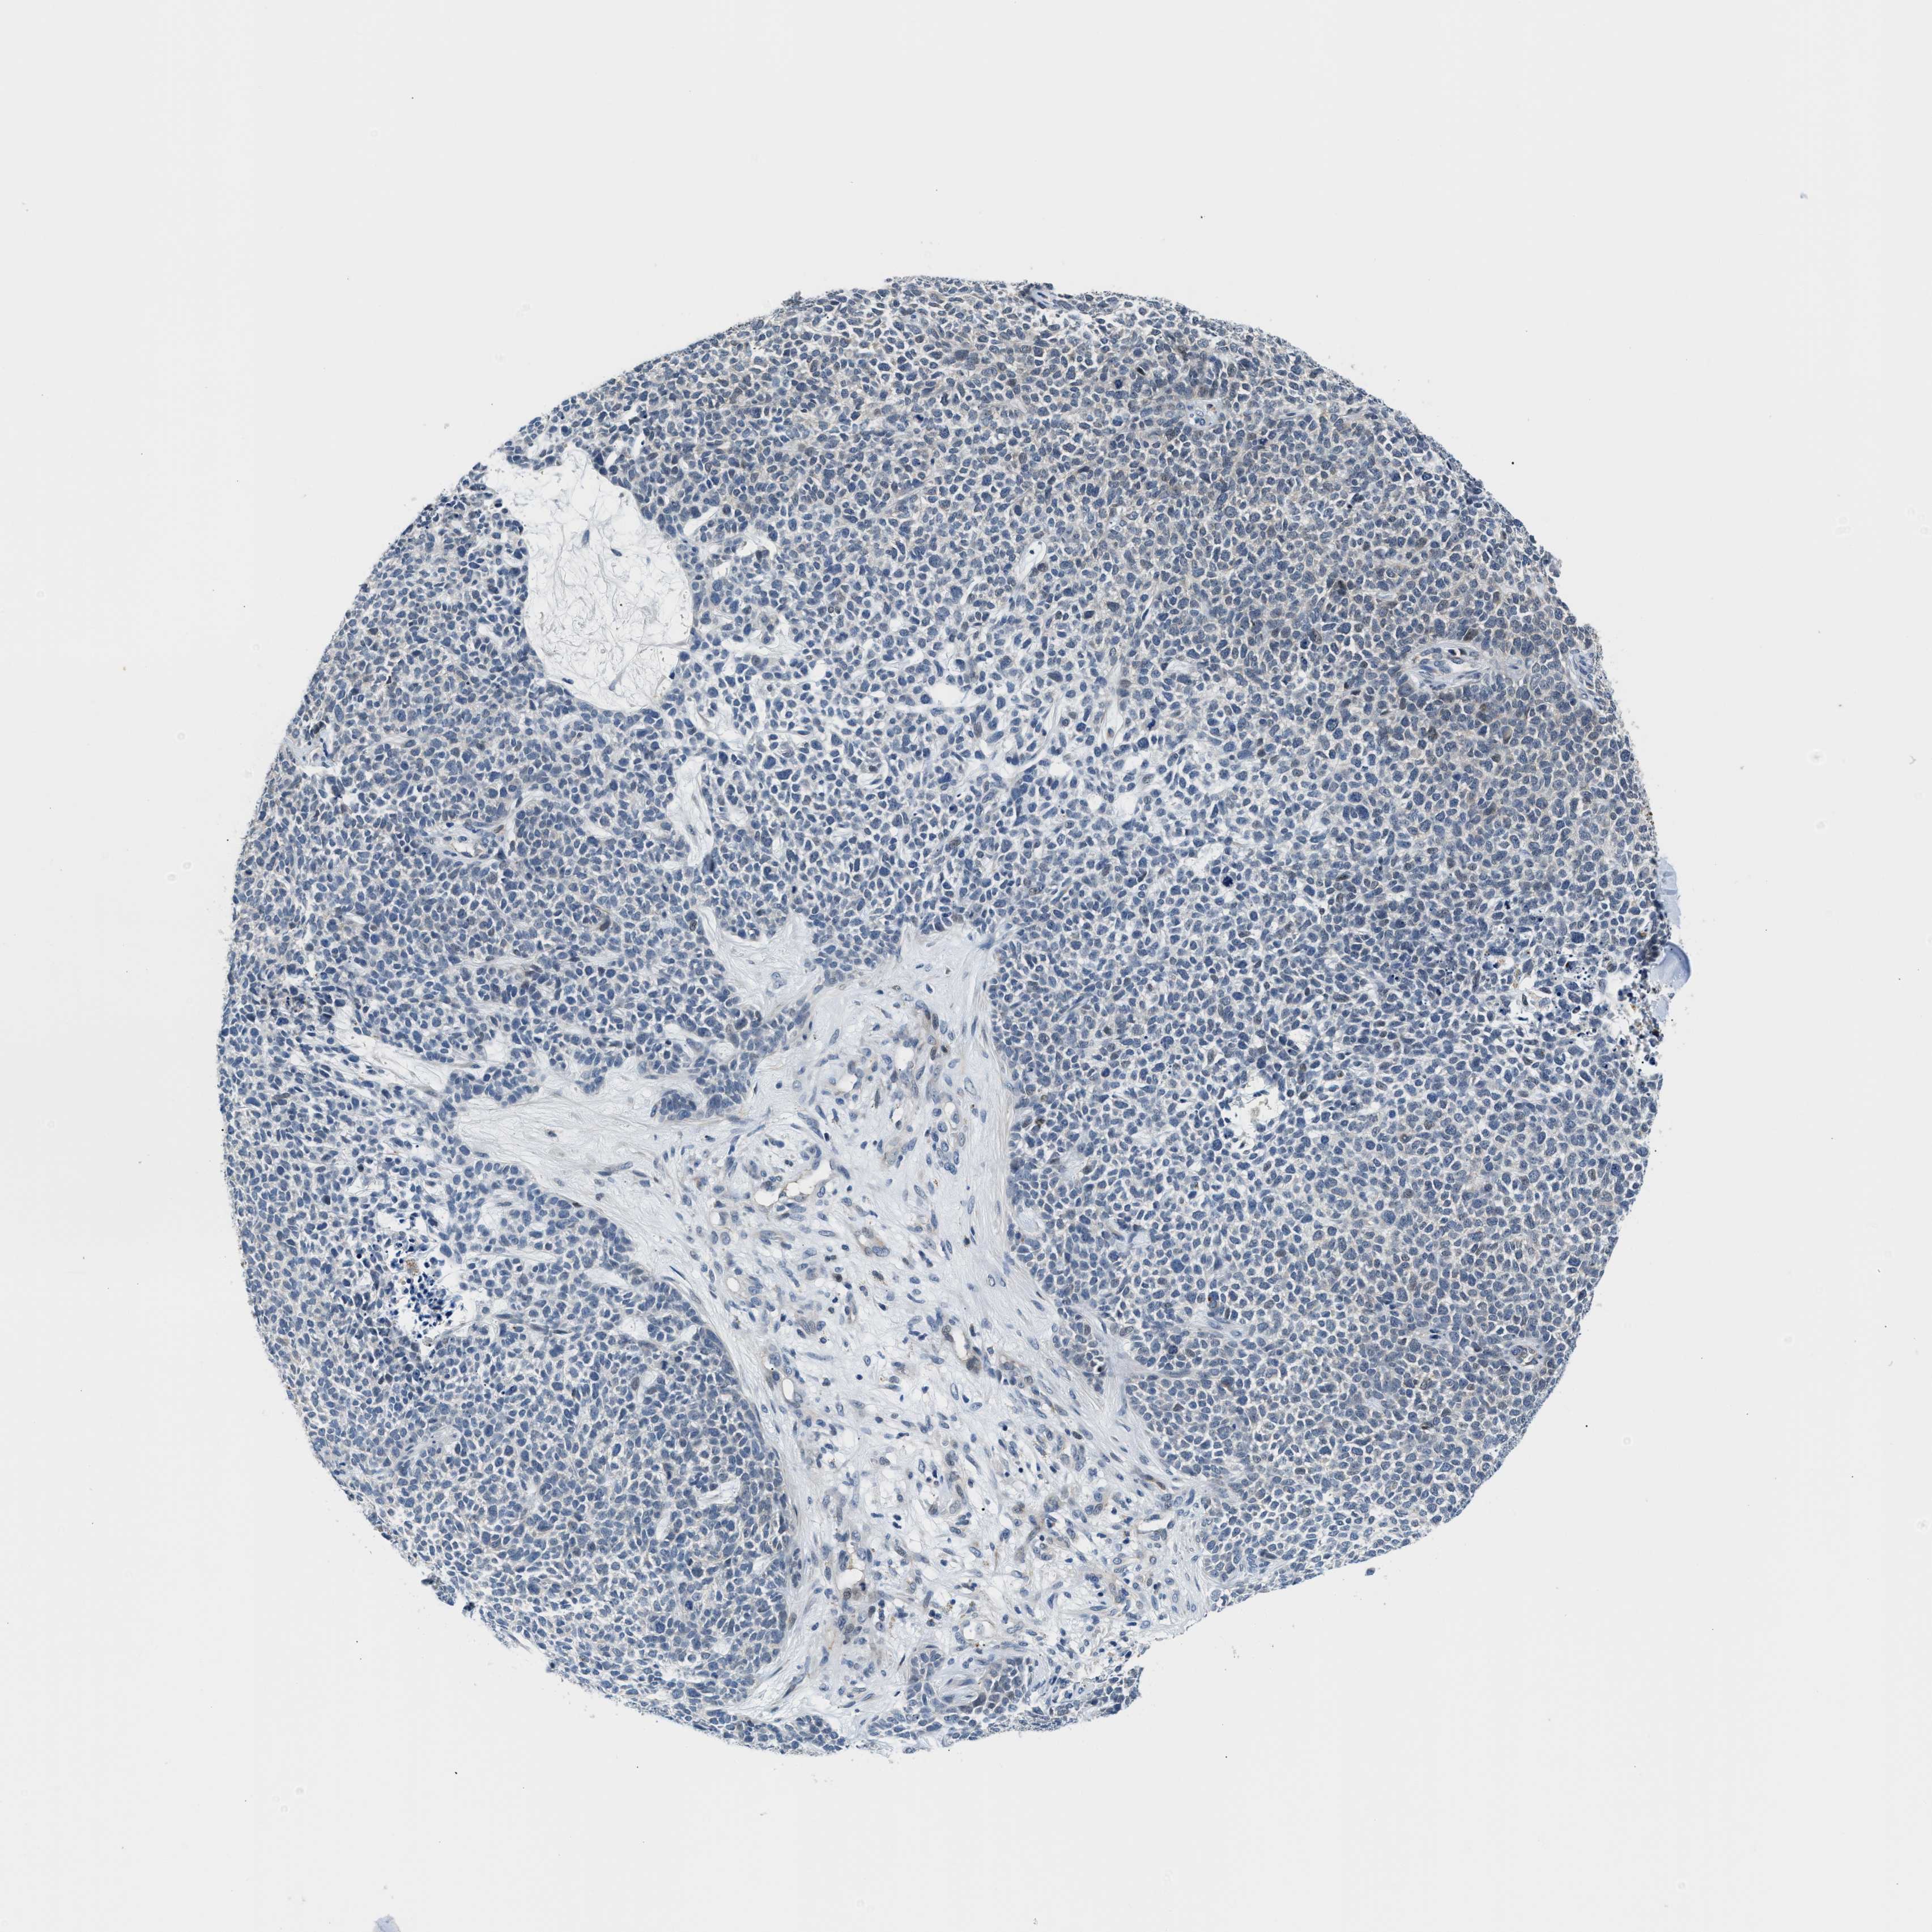

SKIN CANCER - Protein expressioni

A mouse-over function shows sample information and annotation data. Click on an image to view it in a full screen mode. Samples can be filtered based on level of antibody staining by selecting one or several of the following categories: high, medium, low and not detected. The assay and annotation is described here.

Each image is clickable and will lead to virtual microscopy that enables deeper exploration of all samples and also displays staining intensity scores, fraction scores and subcellular localization as well as patient and tissue information for each sample.

Antibody HPA044244

Basal cell carcinoma